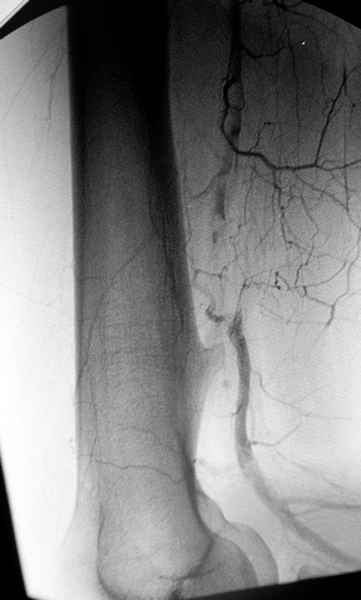

Обычная Solitary Osteochondroma или экзостоз относится к часто встречающимся доброкачественним опухолям. При давлении на нерв или на сосуды могут быть характерные симптомы, а так клинически не проявляется и обнаруживается случайно при исследованиях по другим поводам.

Пару лет назад наблюдал больную 35 лет, физически

здоровую, отслужила в Ираке, жаловалась на слабость в конечности во время физических нагрузок.

Ангиография подтвердила васкулярную аневризму в

результате давления экзостозом. Совместно с сосудистым хирургом была проведена плоскостная резекция с дальнейщим восстановлением сосуда венозным графтом.